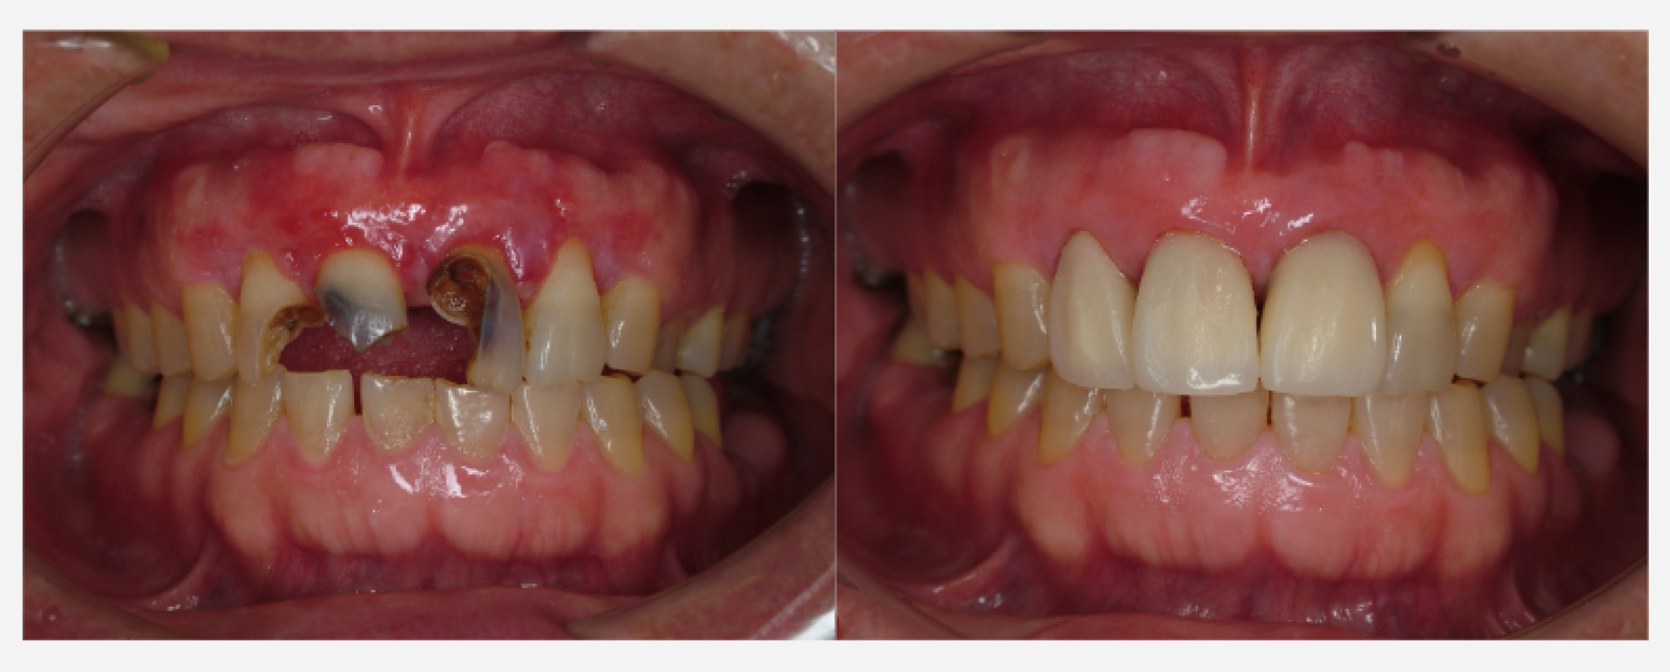

治療前治療後

| 治療内容 | 前歯インプラント治療/下前歯矯正治療 |

|---|---|

| 患者様の年齢 | 19歳 |

| 患者様の性別 | 女性 |

| 治療期間 | 1年 |

| 治療回数 | 矯正治療合わせて45回程度 |

| 治療費用 | インプラント治療50万円/矯正15万円 |